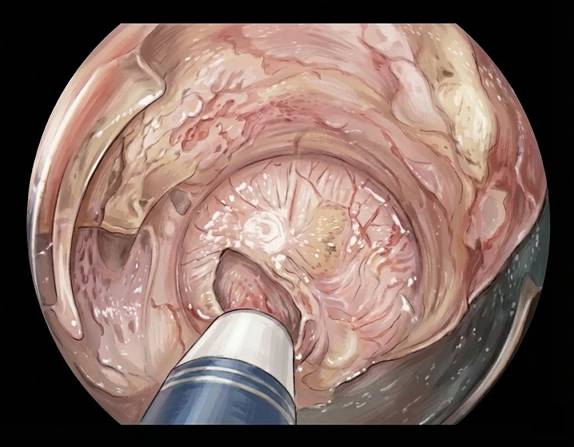

Resección transmural endoscópica (RTMe): extirpar toda la pared en un punto

La RTMe utiliza un dispositivo que actúa como un “cepo” o un clip grande. Atrapa la pared del colon donde está el pólipo, la cierra en bloque y, por encima del cierre, se reseca la pared con un lazo. Suele emplearse en lesiones no muy grandes, habitualmente por debajo de dos centímetros, que no se sobreelevan fácilmente por la presencia de fibrosis.

Las series publicadas muestran una tasa alta de cierre correcto y extirpación de la lesión, aunque no todas las piezas resultan impecables, con sus márgenes de resección negativos. También existe un porcentaje nada despreciable de complicaciones relevantes, como perforación, sangrado, apendicitis (cuando se extirpan lesiones en la zona del apéndice) o necesidad de cirugía urgente. Es, por tanto, una herramienta muy útil en casos seleccionados y en centros con cirugía colorrectal disponible ante cualquier contratiempo.